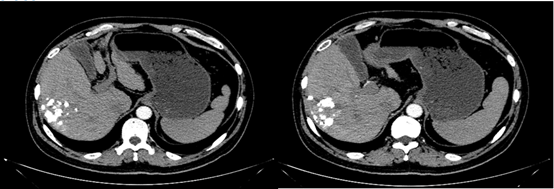

2018-12-11腹部CT检查提示,肝硬化、脾略大、门静脉高压;肝S6占位性病变,考虑原发性肝癌;肝S7段2枚结节;肝多发小囊肿,肝右叶钙化灶;双肾囊肿。

图片

图:腹部CT检查(2018-12-11)

诊断:原发性肝细胞癌Ⅰb期(Child-Pugh A/B)